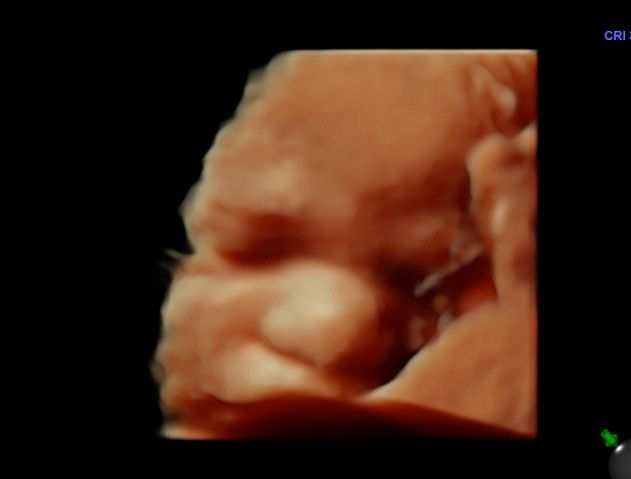

Foto e video

• Ecocardiografia fetale

• Ecografia morfologica